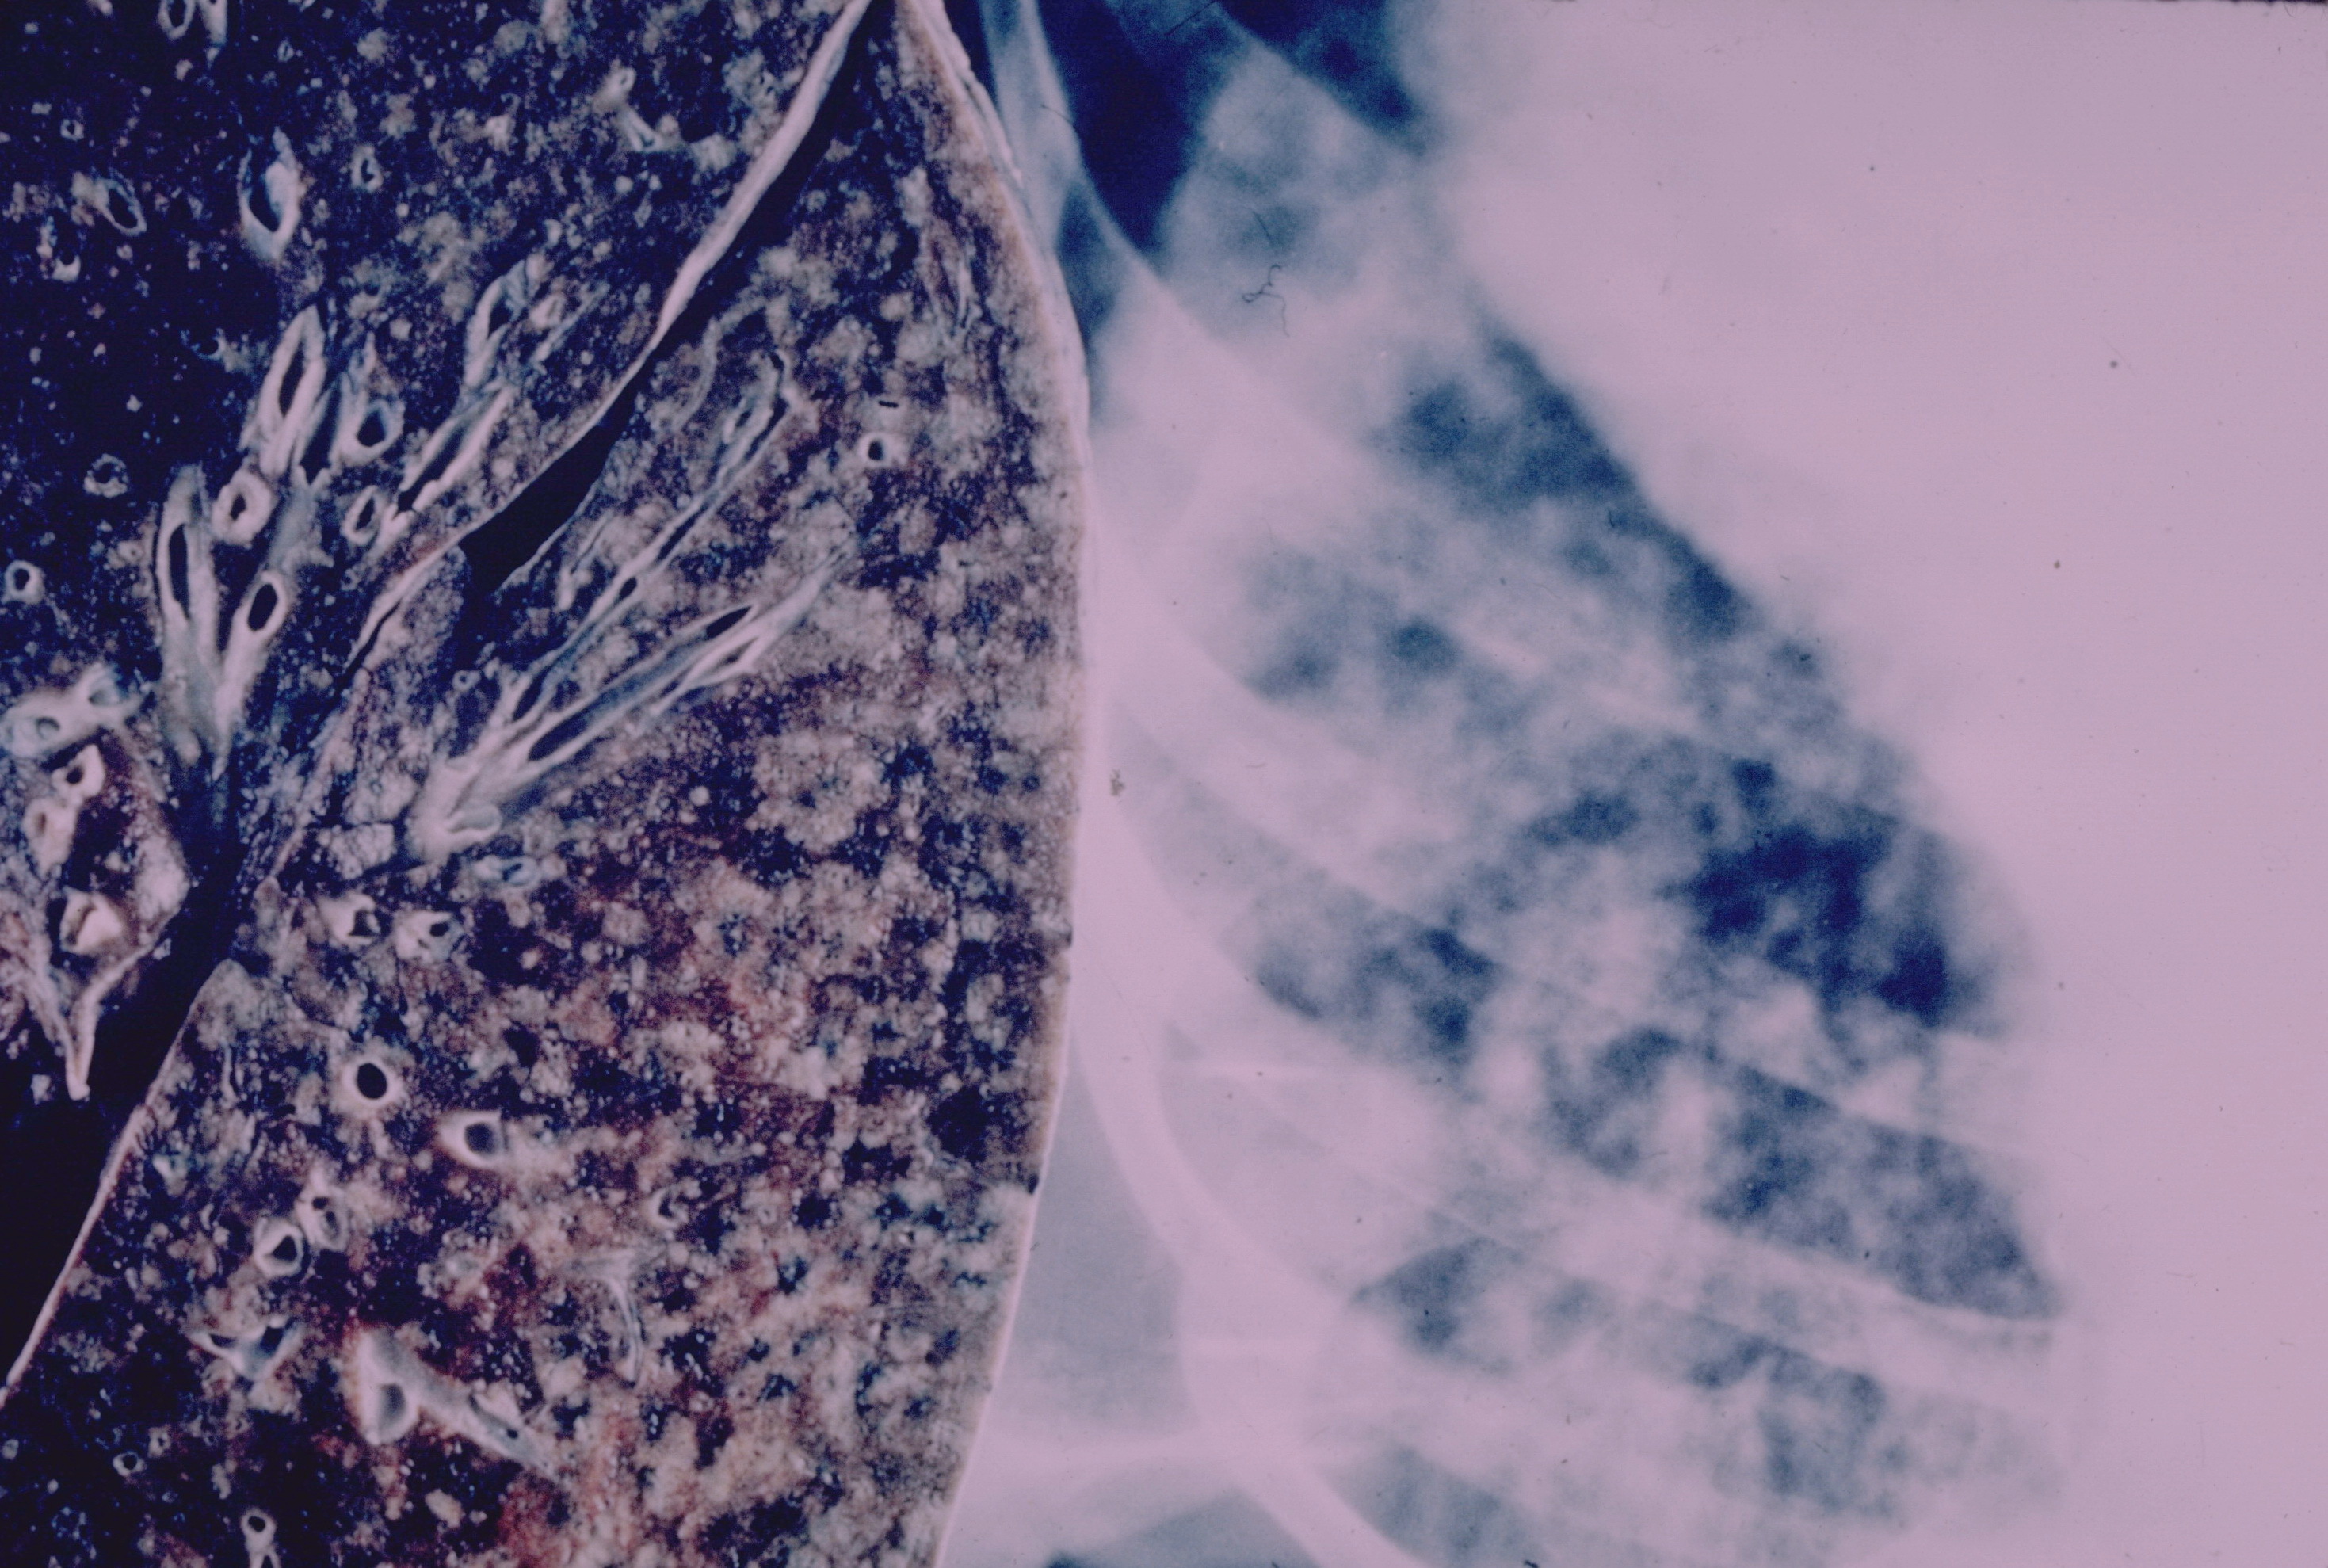

Фото: Lung - Miliary tuberculosis, Yale Rosen from USA, Creative Commons Attribution-Share Alike 2.0 Generic license.